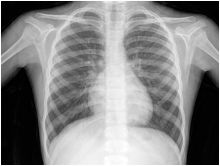

افتراضي أشعة X ترفع معدل الإصابة بسرطان الثدي عند السيدات

كشفت دراسة أوروبية حديثة أن السيدات اللاتي تعاني تحوراً جينياً معيناً يكُن أكثر عرضة للإصابة بسرطان الثدي إذا ما تعرضن للإشعاع الصادر عن أشعة X على الصدر أو أشعة تصوير الثدي mammograms قبل بلوغ سن الثلاثين.

ومن المعروف أن الإشعاع يمثل عامل خطورة للإصابة بسرطان الثدي بين السيدات جميعاً. لهذا توصي بعض الدول بعدم إخضاع السيدات في سن أقل من الثلاثين لصور الأشعة على الثدي للكشف المبكر عن الأورام السرطانية.